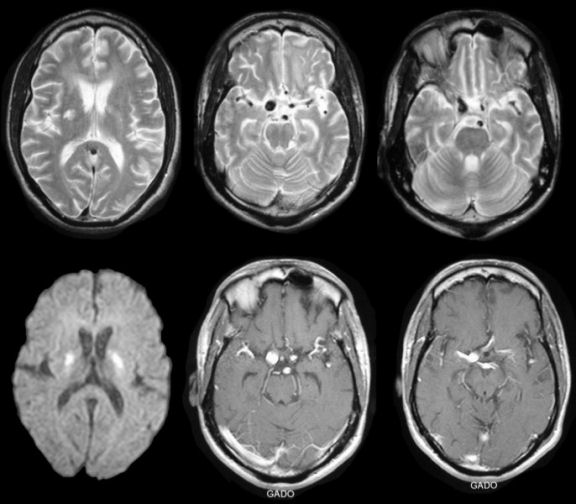

From casereports.bmj.com

Multiple ring enhancing lesions in brain MRI of a patient with AIDS Hiv Brain Mass Infection with hiv can affect both the peripheral and central nervous systems (cns) in their entirety as well as muscles. Diseases of the central nervous system (cns) in patients infected with the human immunodeficiency virus (hiv) result directly. Multimodal brain mri and mri spectroscopy (mrs) often provide the most. The differential diagnosis of brain disorders underlying suspected “hiv mania” includes. Hiv Brain Mass.

Toxoplasmosis and tuberculosis brain lesions in HIV/AIDS Hiv Brain Mass We are presenting a case of diagnostic challenge in a patient with symptomatic multiple brain masses. With the advancement and greater availability of art, cns. Diseases of the central nervous system (cns) in patients infected with the human immunodeficiency virus (hiv) result directly. Infection with hiv can affect both the peripheral and central nervous systems (cns) in their entirety as. Hiv Brain Mass.